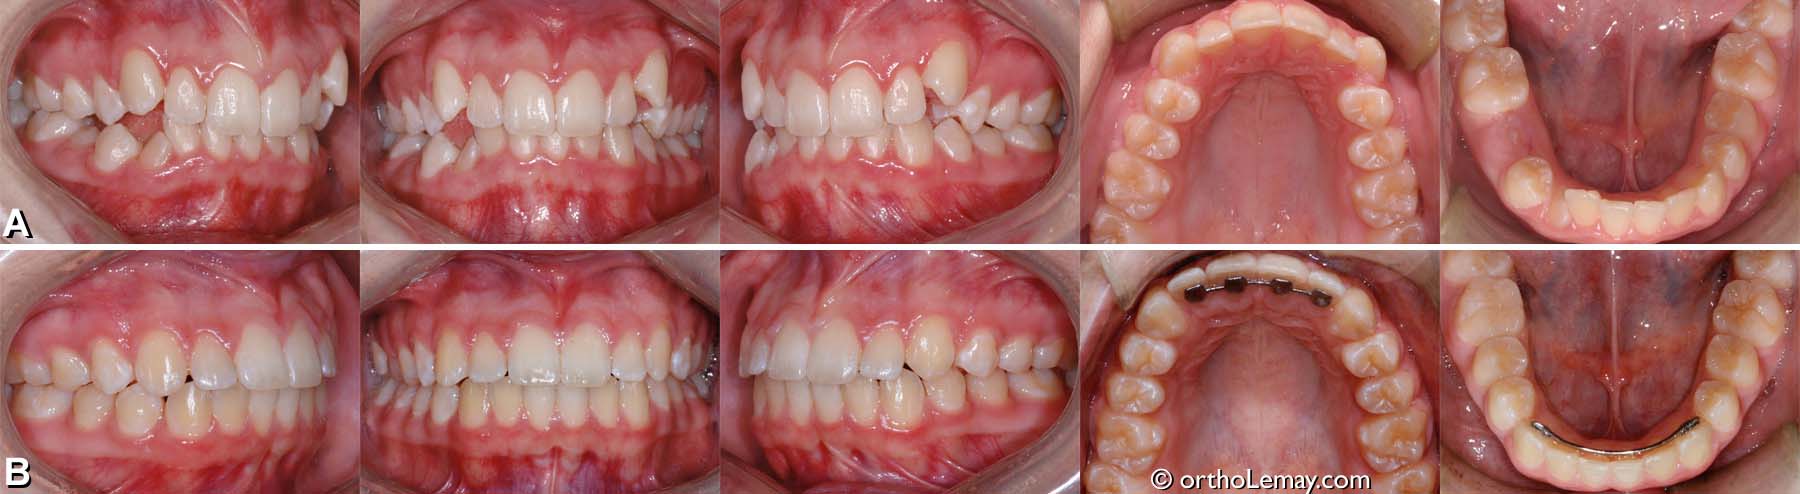

Exemple de traitement de malocclusion classe 1 (21)

(A) Légère malocclusion classe 1 , adolescente de 13 ans avec chevauchement dentaire.

(B) Correction du chevauchement, de l’overbite et des lignes médianes. L’espace entre l’incisive latérale supérieure gauche et la canine est dû à la forme de la latérale. Ceci pourrait être corrigé avec du matériau composite par le dentiste si cela était un problème esthétique pour la patiente.